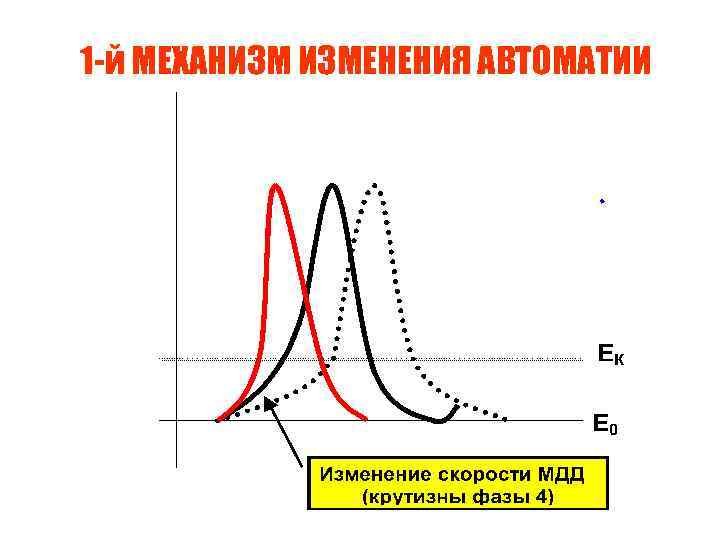

1 -й МЕХАНИЗМ ИЗМЕНЕНИЯ АВТОМАТИИ

1 -й МЕХАНИЗМ ИЗМЕНЕНИЯ АВТОМАТИИ